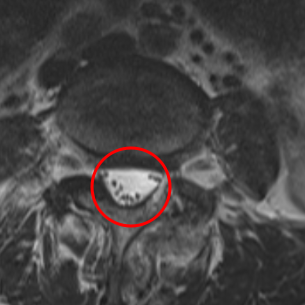

治療後

手術の翌日には、座っていると少し痛みが出るものの、これまであった左足の痛みはなくなったそうです。さらに術後1か月目には腰痛は10から2に、足の痛みは10から0になりました。術後の腰椎MRIでもL4/5が減圧していることを確認しました。さらに術後2か月目は、腰痛の痛み指数も0になりました。